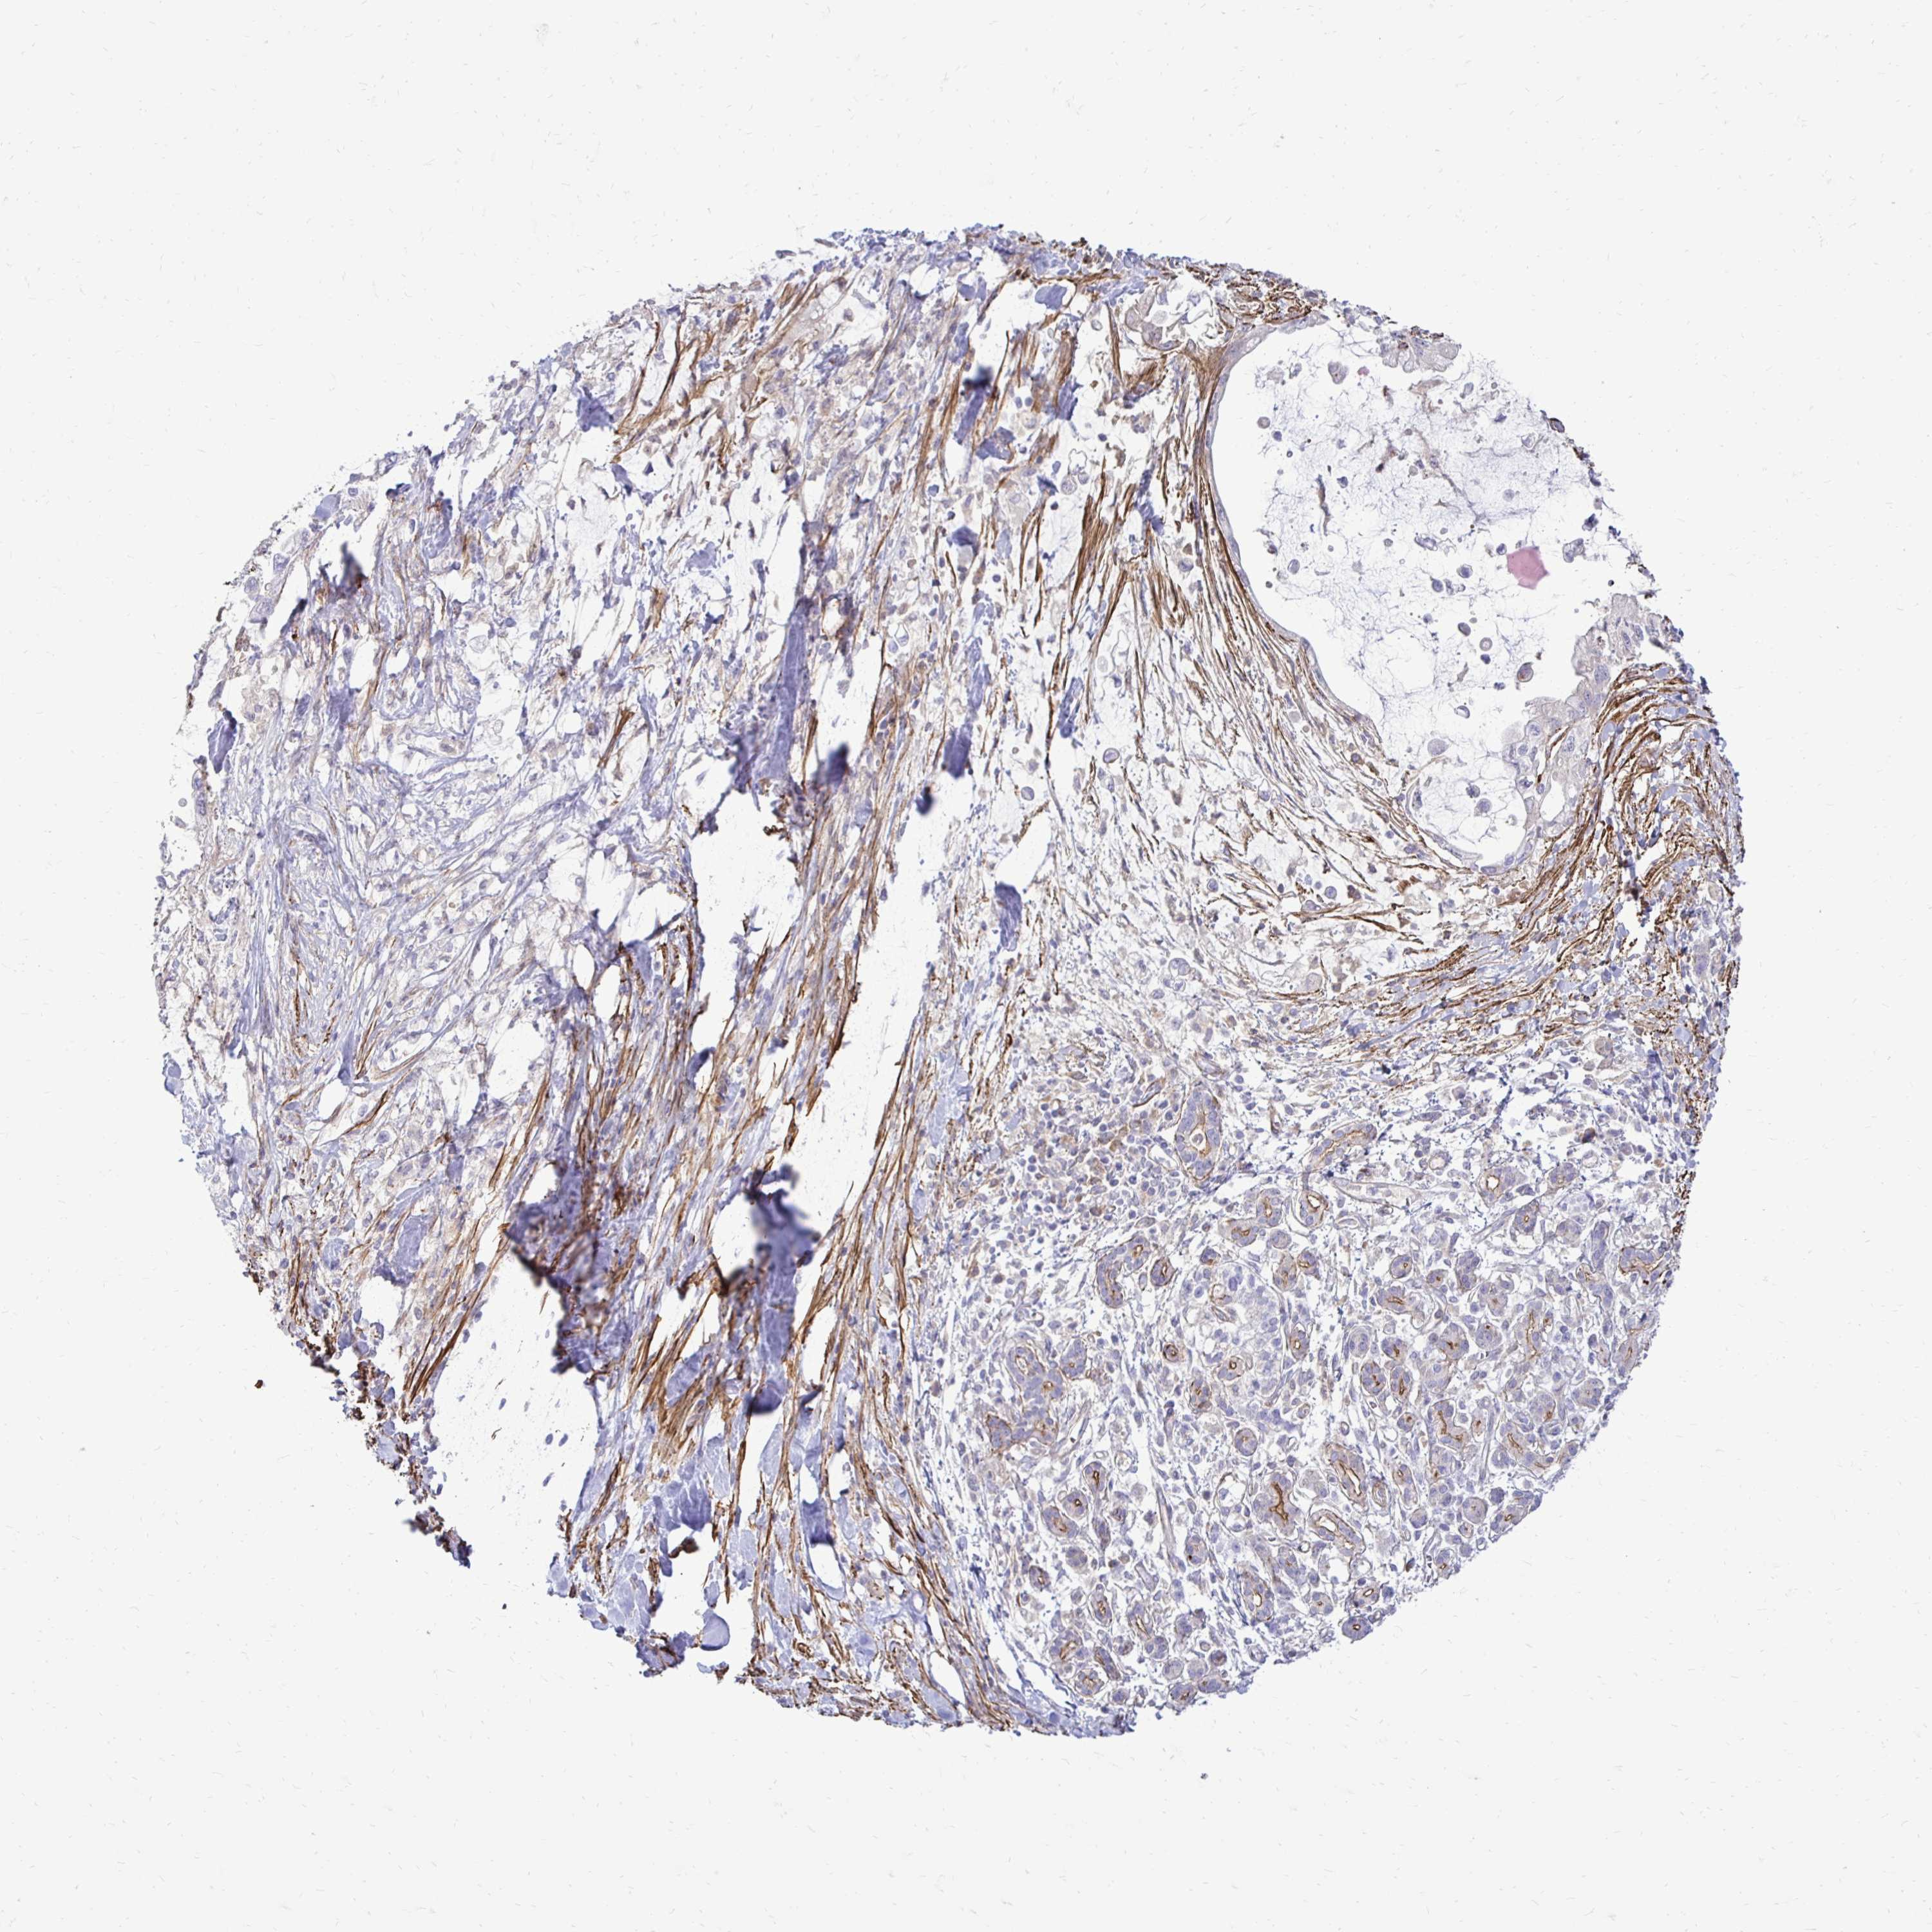

PANCREATIC CANCER - Protein expressioni

A mouse-over function shows sample information and annotation data. Click on an image to view it in a full screen mode. Samples can be filtered based on level of antibody staining by selecting one or several of the following categories: high, medium, low and not detected. The assay and annotation is described here.

Note that samples used for immunohistochemistry by the Human Protein Atlas do not correspond to samples in the TCGA dataset.

Antibody stainingi

Antibody staining in the annotated cell types in the current human tissue is reported as not detected, low, medium, or high, based on conventional immunohistochemistry profiling in selected tissues. This score is based on the combination of the staining intensity and fraction of stained cells.

Each image is clickable and will lead to virtual microscopy that enables deeper exploration of all samples and also displays staining intensity scores, fraction scores and subcellular localization as well as patient and tissue information for each sample.

Antibody HPA051322

Antibody CAB017111

Staining

High

Medium

Low

Not detected

Intensity

Strong

Moderate

Weak

Negative

Quantity

>75%

75%-25%

<25%

None

Location

Nuclear

Cytoplasmic/membranous

Cytoplasmic/membranous,nuclear

Adenocarcinoma, NOS